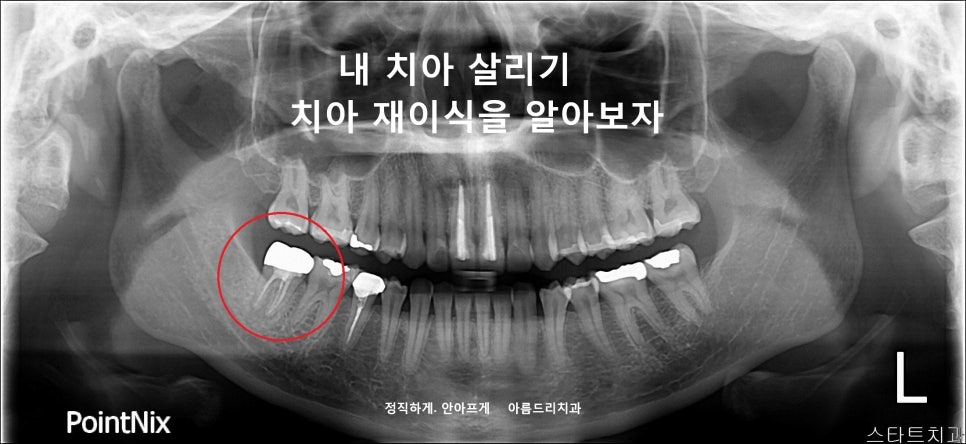

재식_전 파노라마 재식_후 파노라마

이렇게 이식된 치아는 주변 잇몸뼈와 치아가 잘 붙기를 기다려야 합니다. 임플란트와 마찬가지로 3-4개월 정도 기다려야 합니다.

재식후 한 달 뒤

재식 후 환자의 치아 상태를 확인해야 하므로 정기적인 체크를 받으셔야 합니다. 치아재식은 신경치료로 치아를 살릴 수 없어 임플란트를 하기 전 선택할 수 있는 치료법입니다.

다만, 모든 환자가 가능한 것은 아닙니다. 위에서 설명드린 바와 같이 건강한 잇몸뼈와 손상 없는 치아 뿌리 환자의 상태 조건과 발치시 손상을 주어선 안되기 때문에 재식의 노하우, 많은 케이스를 해보신 의사에게 받으셔야 합니다.

재식의 다량 케이스를 가지고 있는 아름드리치과와 재식술을 상담하세요.